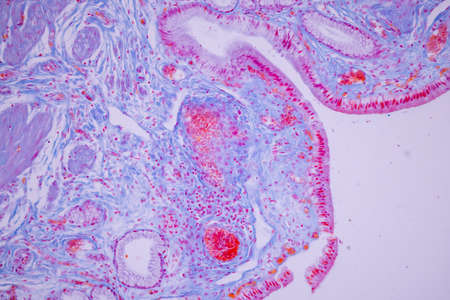

Columnar epithelium of human gall bladder under the microscope in Lab.

Characteristics Tissue of Olfactory epithelium Human under the microscope in Lab.